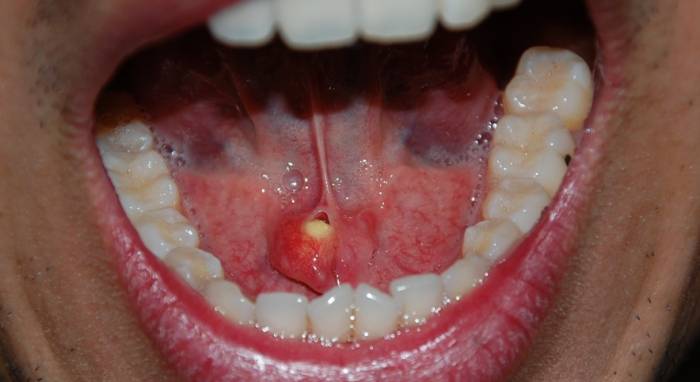

Фото и рентген

Фотографии в статье иллюстрируют развитие слюннокаменной болезни. Рентгенологические исследования необходимы для диагностики, но их следует дополнять другими методами.

| Появление камня в устье протока слюнной железы (видимый) | Образование камня в протоке | Хирургическое удаление камня |